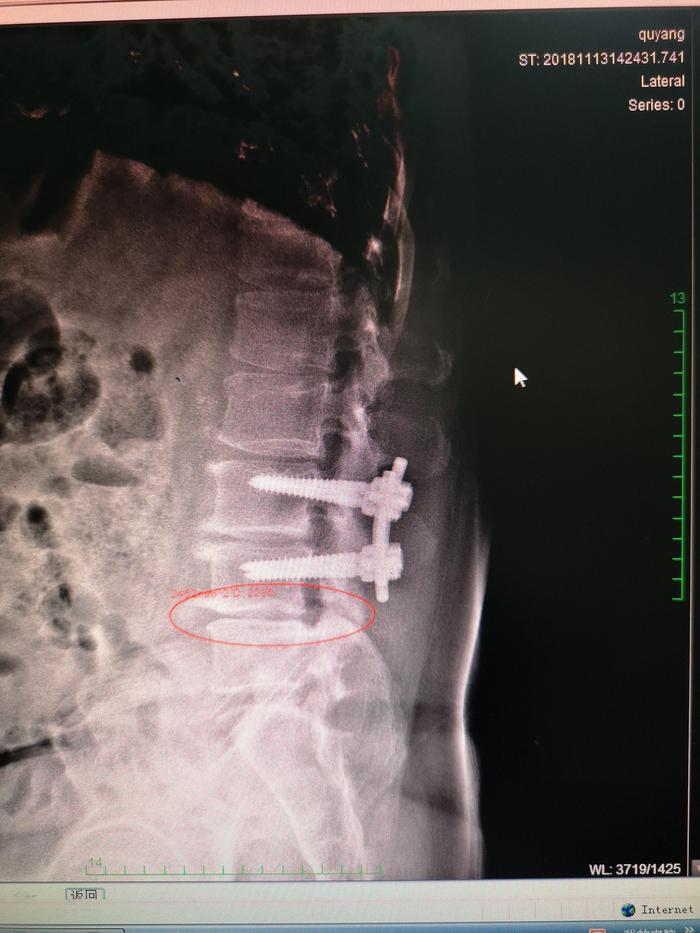

下面的是一位腰间盘手术后进行内固定治疗,术后1年的患者的X光片子。

我们可以对照一下手术前和手术之后我标记的部位的关节的改变

开x光片上,我们可以看到治疗前腰4-5椎体间关节是病变不明显的,那么治疗之后椎体间出现了间隙变窄,硬化,增生加重,而脊柱侧弯骨盆旋移都没有得到纠正。术后不到1年再次出现腰痛,不能背伸,也不能侧弯。

分析运动力学原因是因为第三第四,腰椎被固定之后,这两节腰椎的力量通过杠杆的作用都传达到第4、5腰椎上导致这一节段的腰椎负荷加重,出现不平衡损伤进一步加重,此类患者跟我一再强调,他手术做好了,腰间盘突出就好了,事实上并非如此,因为可以引起腰痛的疾病非常多,所以也不是做掉椎间盘手术腰就一定会好了。